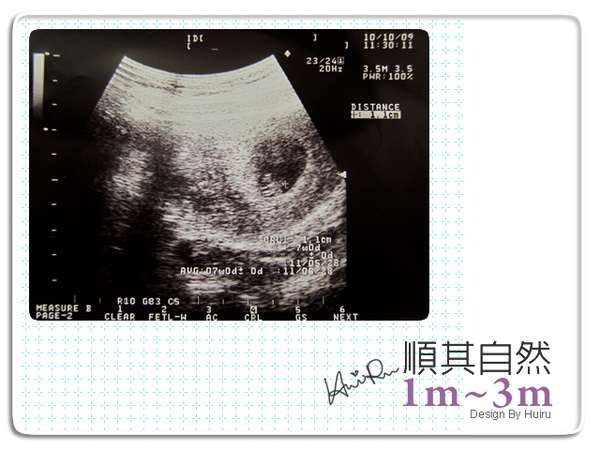

10月9日Mon

mi跟爸比跟我一起去產檢,哇~bb出現了咧,這次是1.1cm,我問了醫師,這次怎比上次小,陳醫師說,因為上次只是胚胎,現在胎兒形成了這是裡面的小bb,喔~原來如此,醫師看到mi跟爸比在場,便放大了bb的心跳聲給他們聽,只見mi一臉狐疑,到了晚上mi問我,馬麻~為什麼小寶寶會有碰碰~碰碰的聲音,我說,那是小寶寶的心跳聲阿,妳也有,說完便抓起mi的手摸摸自己的心跳,這是心跳知道了嗎。